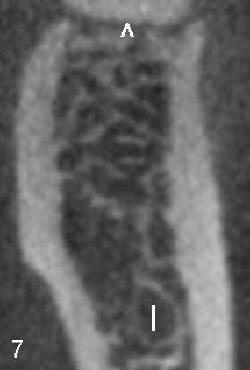

Post-operatively, the patient reports paresthesia of the lower left lip and tightness of the lower left teeth. The extent of paresthesia is marked and recorded 4 days after RCT retreat. In spite of some paresthesia improvement, CBCT is taken 24 days after RCT retreat. It shows that there is a communication (black and white < in Fig.6) between PARL (red <) and the inferior alveolar nerve (I). There are no similar findings (communication or PARL) on the right side (Fig.5).

Cross sections through the furcae of #30 and 19 re-confirm that trabecular patterns are normal under the furca of #30 (< in Fig.7), whereas there is abnormal communication between PARL (above black < in Fig.8) and the inferior alveolar nerve (I).